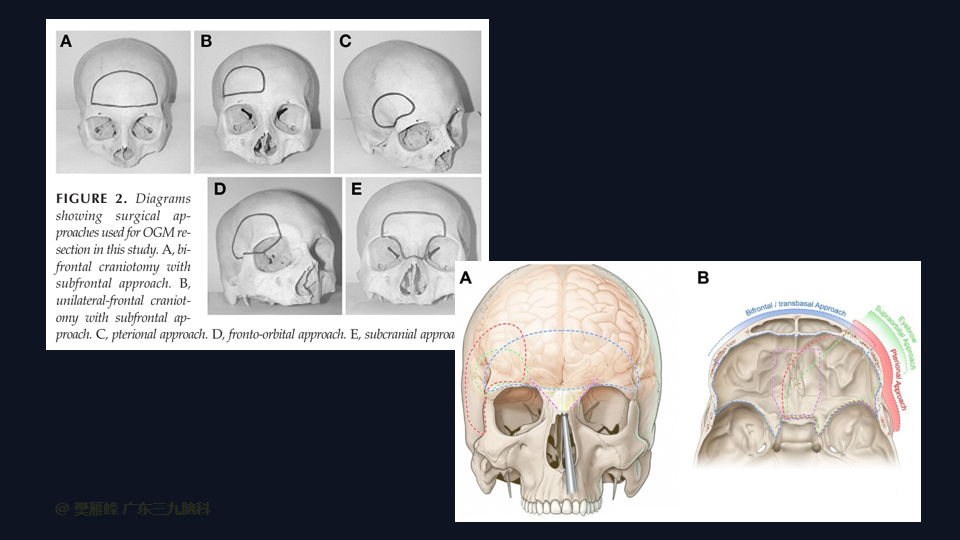

经前纵裂额底入路对于巨大OGMs有效且安全,并且脑牵拉最小,可以达到SimpsonⅠ级切除,患者术后恢复期预后良好,视力改善,嗅觉可以保留。

在这个二维手术视频中,展示了一种经前纵裂额底入路切除巨大嗅沟脑膜瘤的方法。患者是一名52岁的男性,有双眼视物模糊3月、无步态不平衡病史,神经影像学显示前颅窝、双侧鞍旁、桥前池示一巨大团块状等T1长T2,FLAIR序列高信号,明显强化,其内示多发流空信号影,邻近双侧颈内动脉及双侧大脑前动脉被包绕,大小约77×62×51mm的嗅沟脑膜瘤。术中实现肿瘤全切除。术后3月双侧嗅觉基本同术前,双侧视力较术前好转,神经影像学显示肿瘤全切。我们展示了安全的颅神经和肿瘤切除术的细微差别和技术要点,包括:采用降低硬膜开口的颅底法,保留额叶静脉,防止静脉损伤。诊断时,尽管患者嗅觉常常缺失,但仍有至少保留一根嗅觉通路。通过精准的解剖重视A2段的保护。最后,需要多层重建颅底。